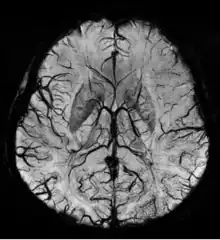

Susceptibility weighted imaging (SWI), originally called BOLD venographic imaging, is an MRI sequence that is exquisitely sensitive to venous blood, hemorrhage and iron storage. SWI uses a fully flow compensated, long echo, gradient recalled echo (GRE) pulse sequence to acquire images. This method exploits the susceptibility differences between tissues and uses the phase image to detect these differences. The magnitude and phase data are combined to produce an enhanced contrast magnitude image. The imaging of venous blood with SWI is a blood-oxygen-level dependent (BOLD) technique which is why it was (and is sometimes still) referred to as BOLD venography. Due to its sensitivity to venous blood SWI is commonly used in traumatic brain injuries (TBI) and for high resolution brain venographies but has many other clinical applications. SWI is offered as a clinical package by Philips and Siemens but can be run on any manufacturer’s machine at field strengths of 1.0 T, 1.5 T, 3.0 T and higher.

The detection of micro-hemorrhages, shearing, and diffuse axonal injury (DAI) in trauma patients is often difficult as the injuries tend to be relatively small in size and can be easily missed by low resolution scans. SWI is usually run at relatively high resolution (1 mm3) and is extremely sensitive to bleeding in the gray matter/white matter boundaries making it is possible to see very small lesions increasing the ability to detect more subtle injuries.